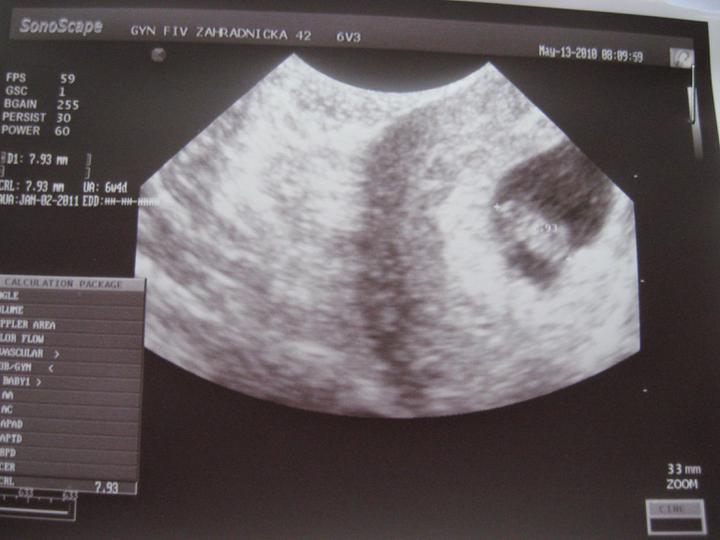

1. čer 2010

mam skvely termin. 1.1.2011. dobre, ze?

zatial vsetko v poriadku